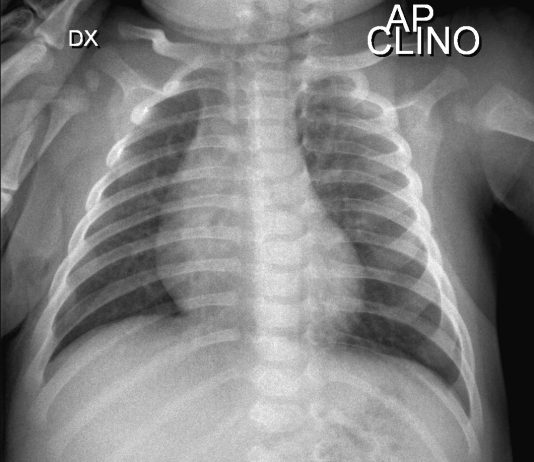

F.Finazzo , G Paviglianiti, M.P.Pappalrdo UOC Radiologia Pediatrica PO G.DI Cristina Arnas Civico Palermo Direttore Dott.ssa M.P. Papplardo

Bimbo di tre mesi ,fratello Covid -19 positivo e genitori Covid-19 positivi ,sintomatici in quarantena presso il loro domicilio.

Viene portato...

Bimbo di sei anni (due fratelli e genitori asintomatici)

Anamnesi patologica prossima:

Febbre da cinque giorni ,trattata con...